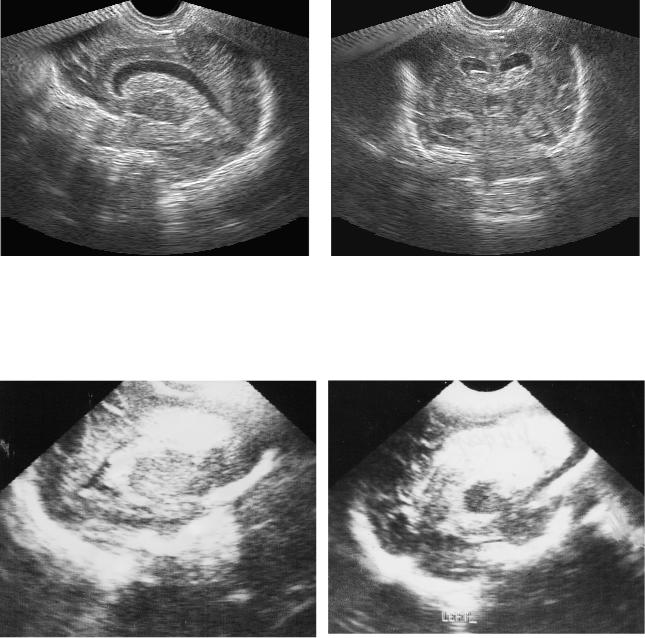

Рис. 10. Исход ПИВК IV ст. (перивентрикуляр-

Рис. 11. Постгеморрагическая прогресси-

ного геморрагического инфаркта). Умеренная

рующая гидроцефалия. Резко выраженное,

непрогрессирующая вентрикуломегалия. По-

балонообразное расширение боковых же-

рэнцефалическая киста.

лудочков. Остатки кровяного сгустка в

просвете желудочка.